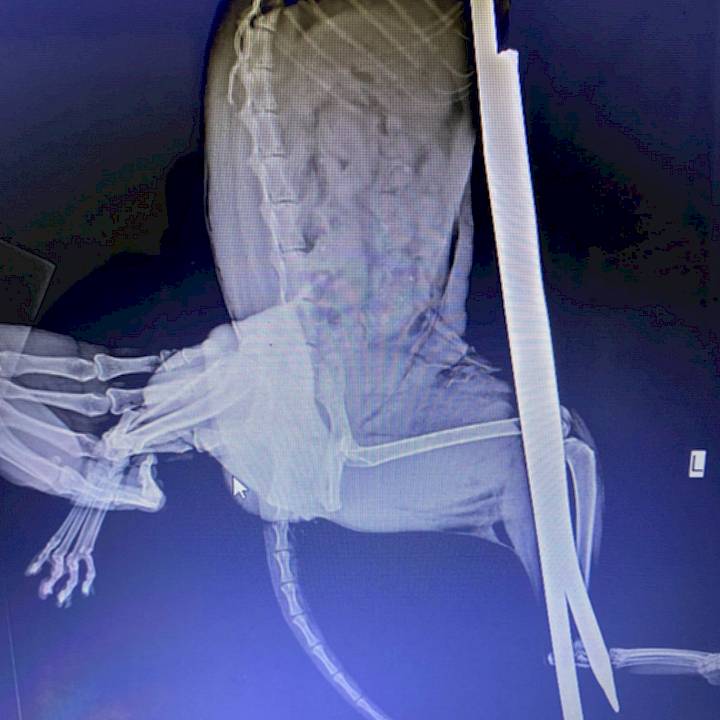

After cutting off the spike, the good citizen brought Lai to our clinic. X-rays showed serious tissue damage, but fortunately no broken bones or trauma to vital organs. Our surgeons were able to remove the spike, without any additional tissue or nerve damage.